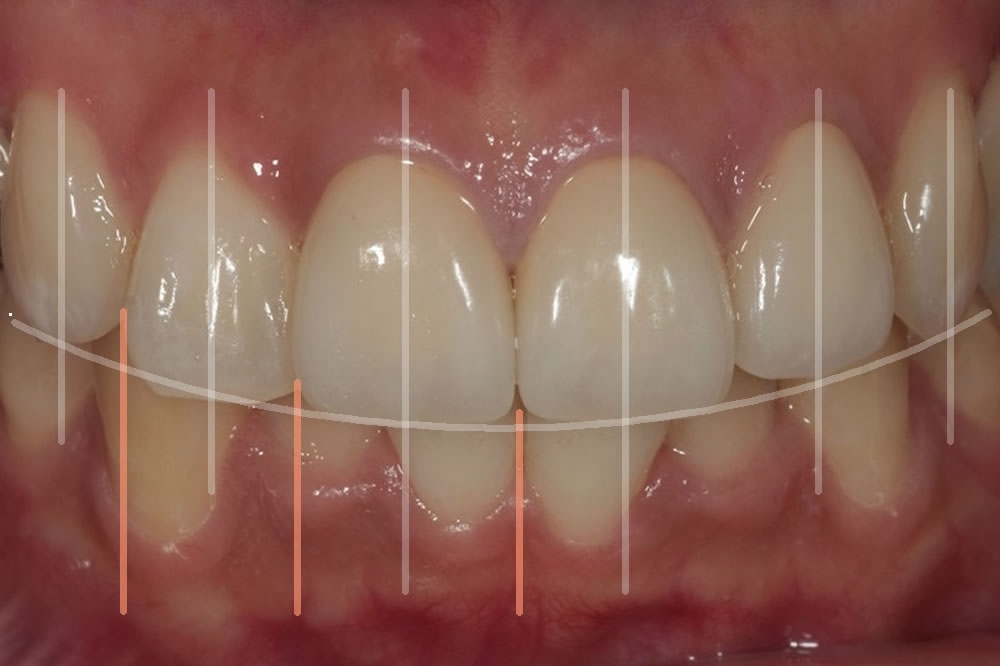

②正中の位置取り

歯の中心ラインと顔の中心ラインのバランスを適切に調整します。

③スマイルライン

笑顔の際に自然で緩やかなカーブができることを意識します。

実際に当院で行った精密審美歯科治療例(前歯のオールセラミッククラウン)

こちらの患者様は転んで前歯をぶつけて他院で修復してもらったが黒ずんで来たということで来院いただいた患者様です。オールセラミック製の被せ物で修復しました。友人からもどれが人工の歯かわからないと評判とのことです。